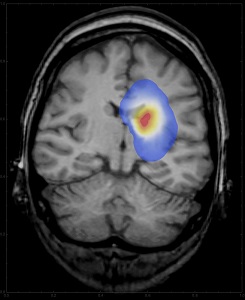

В том случае, если опухоль локализуется в мозге, то у больных могут возникать нарушения речи, памяти, восприятия, сложности с координацией движений и судороги, бред и галлюцинации.